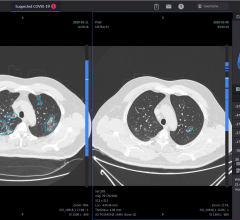

September 22, 2020 — New research from King's College London has found that COVID-19 may be diagnosed on the same ...